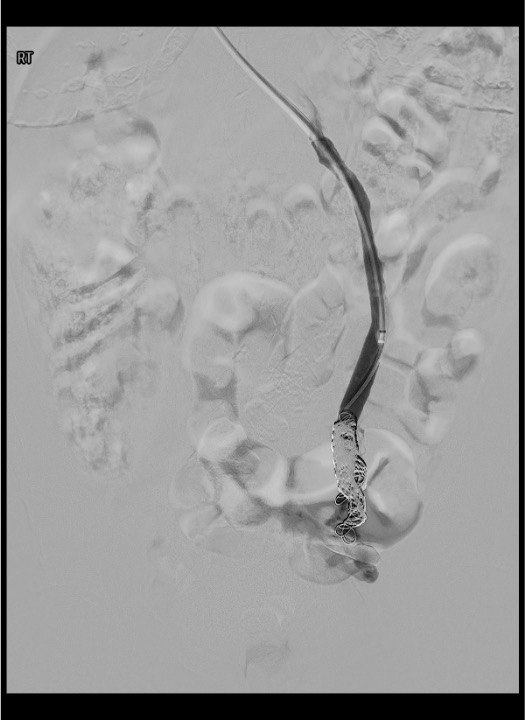

Coil embolization — distal to proximal

Coil malposition or migration

Likely cause: Coil undersized relative to vein diameter; deployed in a location without adequate landing zone; pushed distally during deployment.

Next step: If coil is in a hemostatic position even if not ideal, assess clinically and consider leaving. If coil has migrated to pulmonary vasculature (check chest radiograph post-procedure), small peripheral coils in distal PA branches may be observed. Large coils or centrally positioned PA coils require snare retrieval in the cardiac catheterization lab. Prevention: size coils 20–30% oversized to vessel diameter.

- Coil migration to pulmonary vasculature: rare; prevent by sizing coils 20–30% oversized; if small coil migrates to distal PA, may observe; central PA migration requires snare retrieval